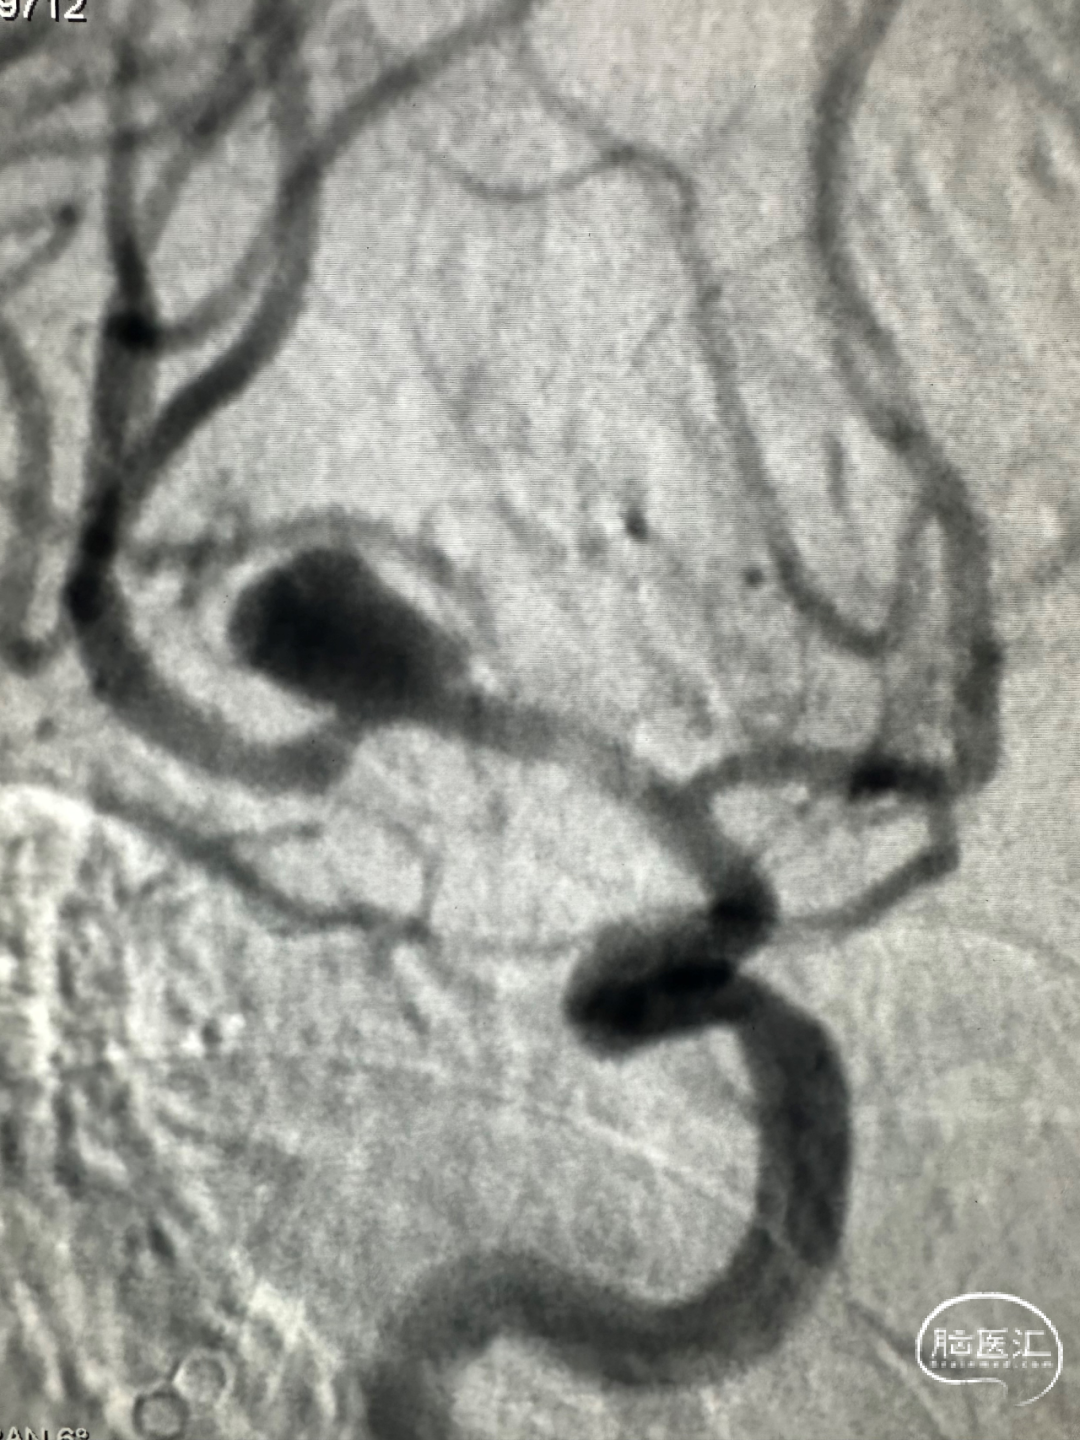

术前影像

右侧M1段分叉部动脉瘤,瘤颈累及M2段上下干支;

动脉瘤大小:8.3mm*8.4mm;